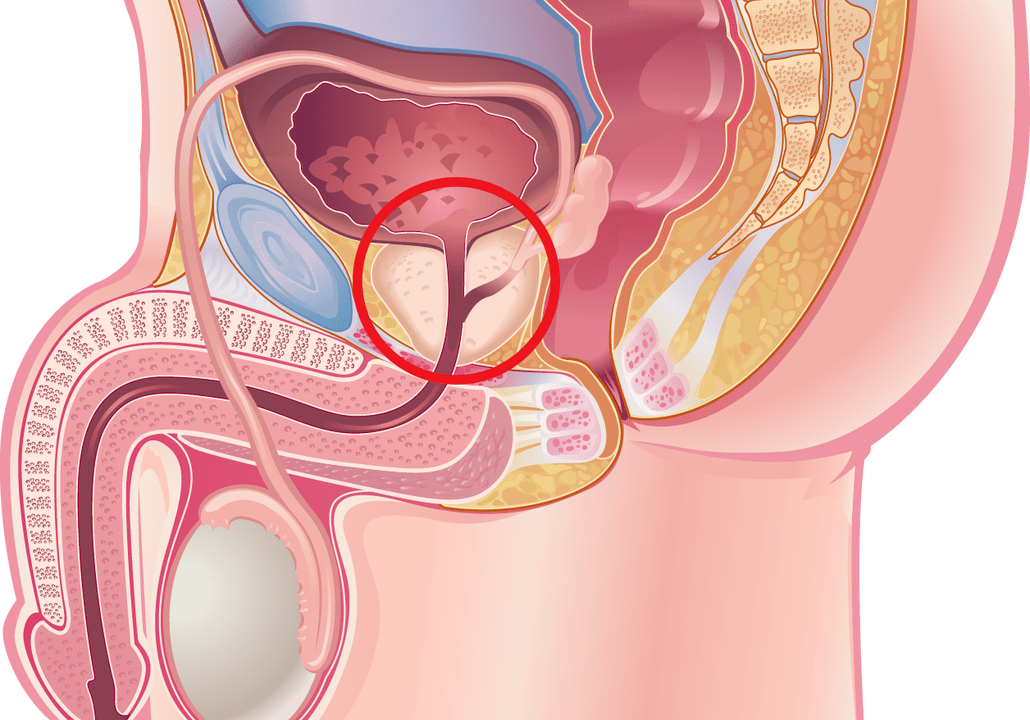

Many men suffer from prostate-related diseases.If there is an inflammatory process in the body that affects the prostate, it is prostatitis.Seeing a doctor will help prevent some of the associated complications by prescribing effective medications.

Prostatitis

Prostatitis can take men over 20 by surprise.To promptly recognize the signs of prostatitis, you need to be familiar with its symptoms, depending on the form of the disease: chronic or acute.